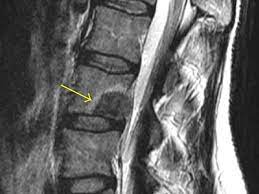

Addressing Metastatic Spine Disease with Precision...